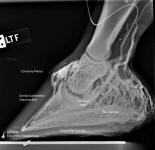

of the Equine Foot

A New 464 Page Textbook, in Full-Color with 630 Pictures and Drawings, by Pete Ramey

A Few Pictures from the book:

Only 570 pictures yet to see... but you get the idea.

Photos referenced in text from Bidwell/Bowker, Bowker, Clayton, Cowles, Hampson, Kellon, Ramey, Ridgway, Sullivan, Taylor, Watts.